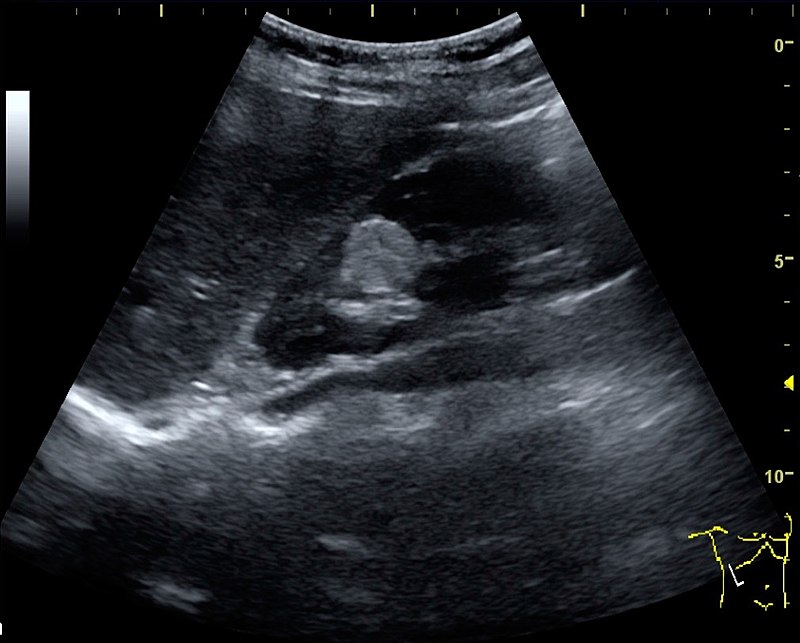

Wilms Tumor

Wilms tumor is a malignant kidney tumor composed of primitive glomeruli, tubules, and stromal cells blastema which is an immature kidney mesenchyme.

The average age of a child who develops a Wilms tumor is 3-years-old.

Symptoms of Wilms tumor include:

- Large mass

- Unilateral flank mass

- Hematuria

- Hypertension brought on by renin secretion

Wilms tumor is associated with WT1 mutation, especially in syndromic cases.